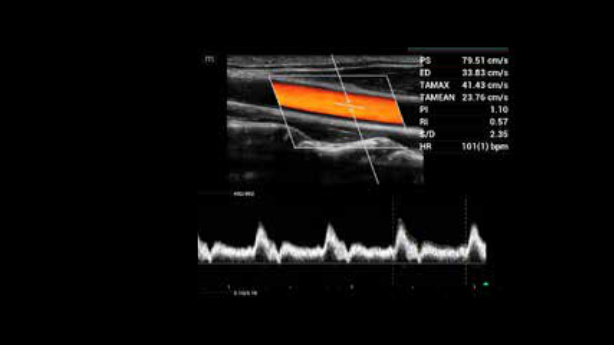

AutoCalc + Smart Track

Istotne jest, aby śledzić pozycję naczyń, używać odpowiedniego kąta oraz dopasowanej wielkości bramki dopplerowskiej. Smart Track robi to automatycznie.

• zeus-fig5-3-1-uk

Doppler tętnicy szyjnej z automatycznymi obliczeniami

• zeus-fig5-3-2-uk

Tętnica szyjna i żyła szyjna